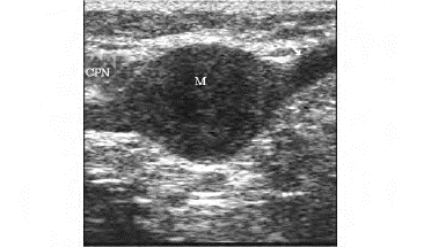

1.39.7七、其他骨、关节、肌腱、周围神经及软组织疾病